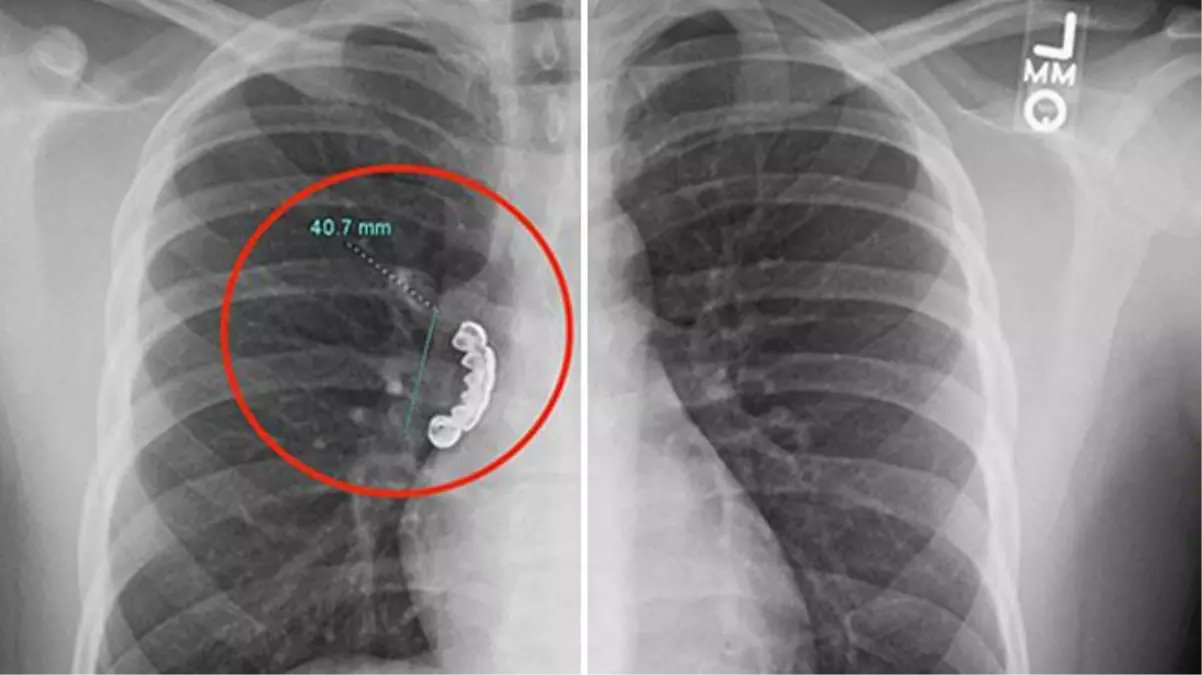

Amerika Birleşik Devletleri'nin (ABD) Wisconsin eyaletinde yaşayan epilepsi hastası genç adam, geçirdiği nöbetin ardından baş gösteren ağır öksürük ve hırıltı şikayetleriyle hastaneye kaldırıldı. 22 yaşındaki adamın çekilen röntgeninde akciğer hava yolunda sıkışmış yaklaşık 4 santimlik takma diş bulunduğu fark edildi.

Doktorlar, hızla bronoskopi yaparak esnek bir tüp yardımıyla sahte dişi çıkardı. Operasyon sırasında bronkospazm (akciğer hava yolundaki kasların sıkışması) yaşayan adam, uygulanan steroit tedavisinin ardından taburcu edildi.